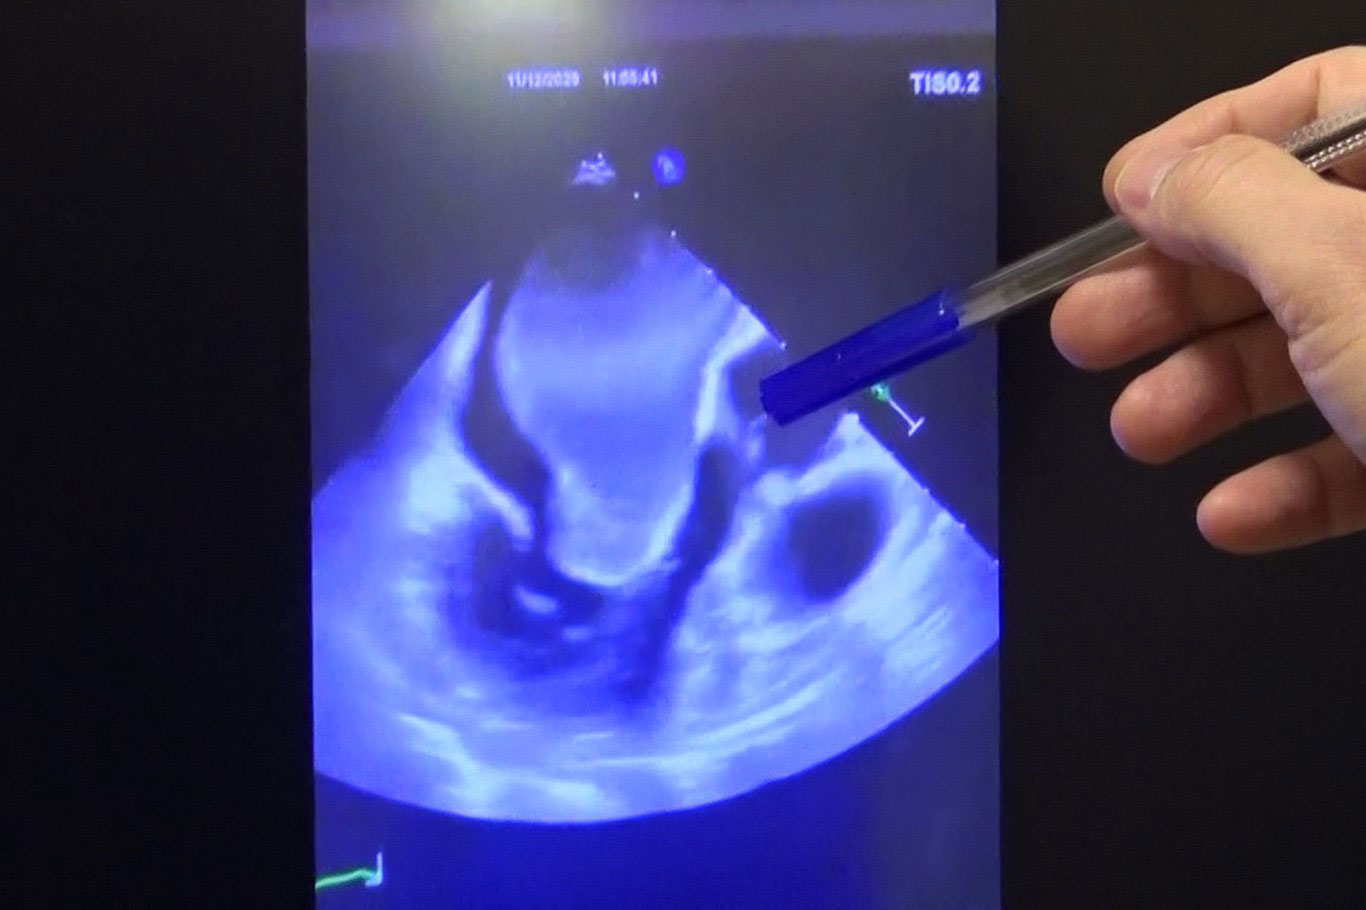

"Sol atriyumu ve kalbi tamamen dolduran devasa bir kitle vardı"

Prof. Dr. Çolak, "Bugün burada Türkiye'de ilk defa yapılan bir işlemden bahsediyoruz. Sol atriyumu ve kalbi tamamen dolduran devasa bir kitle vardı. Kitle çok büyük olduğu için tek parça halinde çıkarılması mümkün değildi, biz de iki parça halinde çıkardık." dedi.

Hastanın daha önce farklı merkezlere başvurduğunu ancak ameliyatın riskli bulunarak kabul edilmediğini aktaran Prof. Dr. Çolak, "Zeynep Hanım bizden önce birkaç merkeze gitmiş. Oralarda ameliyat edilemeyeceği söylenmiş. Gerçekten kitle çok büyüktü. Kalbin her tarafını dolduruyordu ve kan akımına izin vermiyordu. Böyle bir durumda yaşaması adeta mucizeydi." diye konuştu.